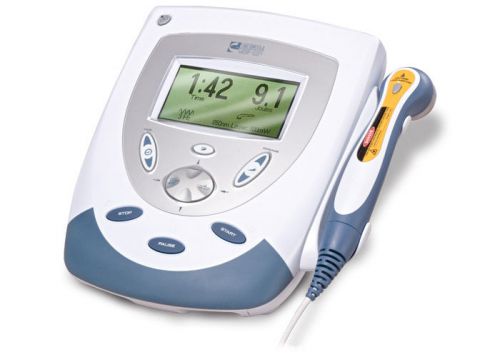

Chattanooga 900 Excel Ultra 4 Four Channel All New Leads Pt Multi Modality

Chattanooga....Gensysis....cold laser....model 27812....9 diode laser applicator